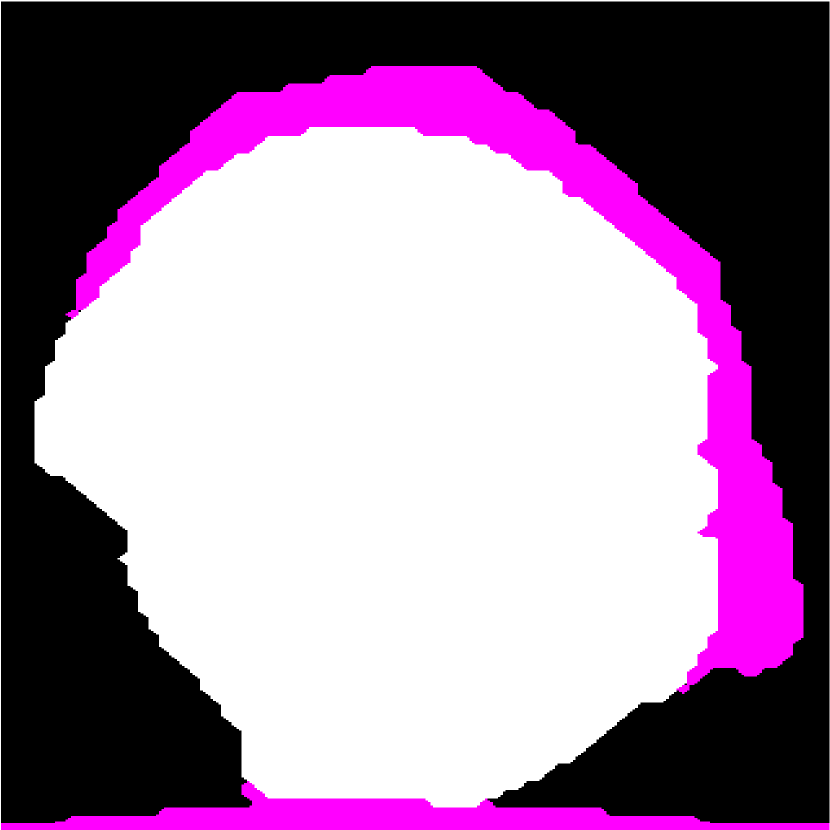

Figure 2: (a) Target HFU image. (b) Manual-segmentation result. (c) The segmentation result obtained by NGC with depth-dependent profile.

Intensity-distribution estimation is another challenge in LN segmentation. To obtain satisfactory segmentation, accurate intensity distributions for the three components of isolated LNs are required. Some clustering algorithms, such as K-means or expectation maximization (EM), may be able to categorize the intensity values of all voxels into three distributions to represent target objects. However, these approaches often yield unsatisfactory segmentation results for larger LNs (Figure 1(c)), where the intensity distribution fluctuates significantly with depth because of acoustic attenuation and focusing effects. In addition, attenuation effects may become so extreme that fat boundaries become invisible. (See the red arrow in Figure 1(a).) To mitigate the attenuation and missing-boundary problems, we used depth-dependent intensity profiles to model the depth-dependent variation of intensity mean and standard deviation in our prior work [11]. Using an expectation-maximization (EM) -based iterative framework, depth-dependent profiles were estimated by a spline-based fitting process from the previous segmentation result, and the segmentation result was obtained by NGC using the estimated depth-dependent profiles. Instead of using an EM-based framework to update profiles, level-set-based approaches can also update profiles during deformation. Bui et al. developed a method, which applied depth-dependent profiles, called statistical transverse slice level-set (STS-LS) [15]. Nevertheless, depth-dependent profiles are unable to deal with intensity inconsistency within the same depth caused by inhomogeneous acoustic attenuation as shown in Figure 2. Figure 2(c) shows the segmentation result obtained using a depth-dependent profile [11]. Compared to the manual segmentation result in Figure 2(b), some fat regions (red arrow) are mislabeled as LNP because the fat on the right (green arrow) at the same depth is much brighter than the fat on the left. In this case, depth-dependent profiles are unable to model the intensity variations accurately. Using local distribution to differentiate LNP and the fat can solve the error caused by intensity inconsistency within the same depth. Bui et al. has used a local-region-based, gamma distribution to segment LNs [13]. Level-set-based methods is good in applying local intensity distributions to differentiate regions. Since level-set-based methods deform the contour gradually, the local distributions can be updated by the boundary accordingly. However, updating distributions in local regions is computationally expensive. Furthermore, using local-region-based distributions with level-set-based methods is likely to result in convergence to a local minimum when the image is noisy. In contrast, GC-based approaches generally set the similarity cost by predefined intensity distributions. Because the boundary is unknown, the local region is hard to be determined in advance.